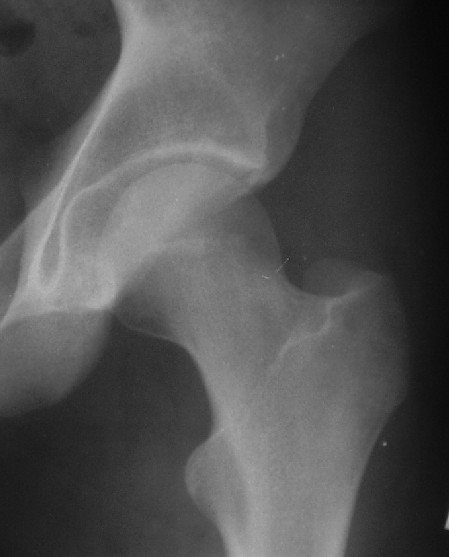

Уважаемые коллеги! Хотел-бы обсудить случай вывиха бедра с переломом вертлужной впадины.

Пациент 16-ти лет попал в ДТП 13.05.05г. Вывих вправлен в больнице по месту жительства в тот же день. Сегодня больной переведен в госпиталь. Вопросы:

Для определения тактики - обязательно - нужен снимок в боковой проекции, скорее операция, в послеоперационном периоде разгрузка, прогноз при правильном ведении - хороший.

Почему отличаются снимки в прямой проекции после вправления здесь и на дополнительном приложении ?

Прямая проекция от 19.05 по всей видимости выполнена с фиксацией деротационной повязкой, что отразилось на положении бедра, кроме этого существенно изменилась позиция таза в сагиттальной и горизонтальной плоскости (постельный режим, уменьшение болевого синдрома).

О диагнозе: в отсутствие КТ, КТ с 3D реконструкцией, с наибольшей вероятностью можно предположить, что откололся фрагмент заднего сектора вертлужной впадины. С позиции современных представлений о механике тазобедренного сустава указанный сектор не является опорным в вертикальном положении. Казалось бы, его необязательно репонировать и фиксировать, тем более размеры фрагмента малы: